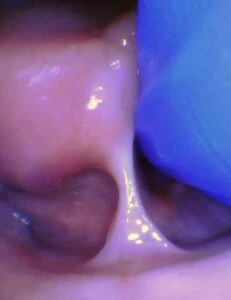

Spectrum of lip restriction in a child

Spectrum of tongue restriction in a child

Posterior tongue-tie in a child seen with lifting the tongue. The posterior or “hidden”tongue-tie can cause the same symptoms including nursing pain and poor weight gain, as a to-the-tip tie in a child